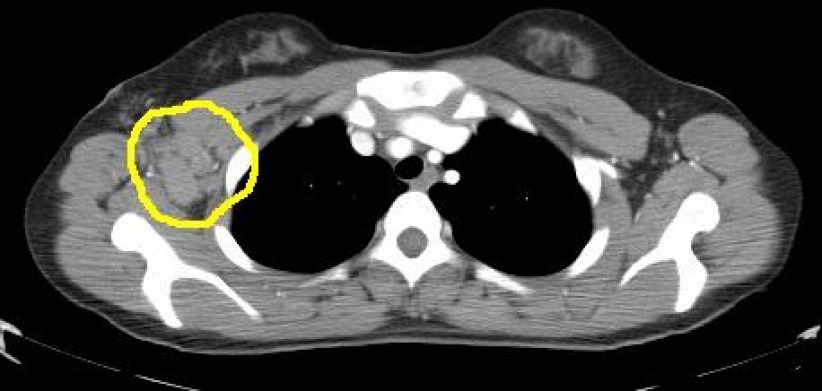

The key finding is, as encircled in this image, a rounded opacity in the right axilla. Here are select CT images demonstrating the presence of several opacities in the right axillary region. The opacities represent lymphadenopathy. Compare with the left axilla where there is no evidence of enlarged lymph nodes.

Diagnosis: Hodgkin's lymphoma (biopsy confirmed). The patient has stage I disease, in other words the disease was limited to a single lymph node group in the right axilla. No additional disease was found in the head, neck, chest, abdomen, or pelvis on CT examination. Clinical examination failed to demonstrate lymphadenopathy in other sites in the appendicular skeleton.